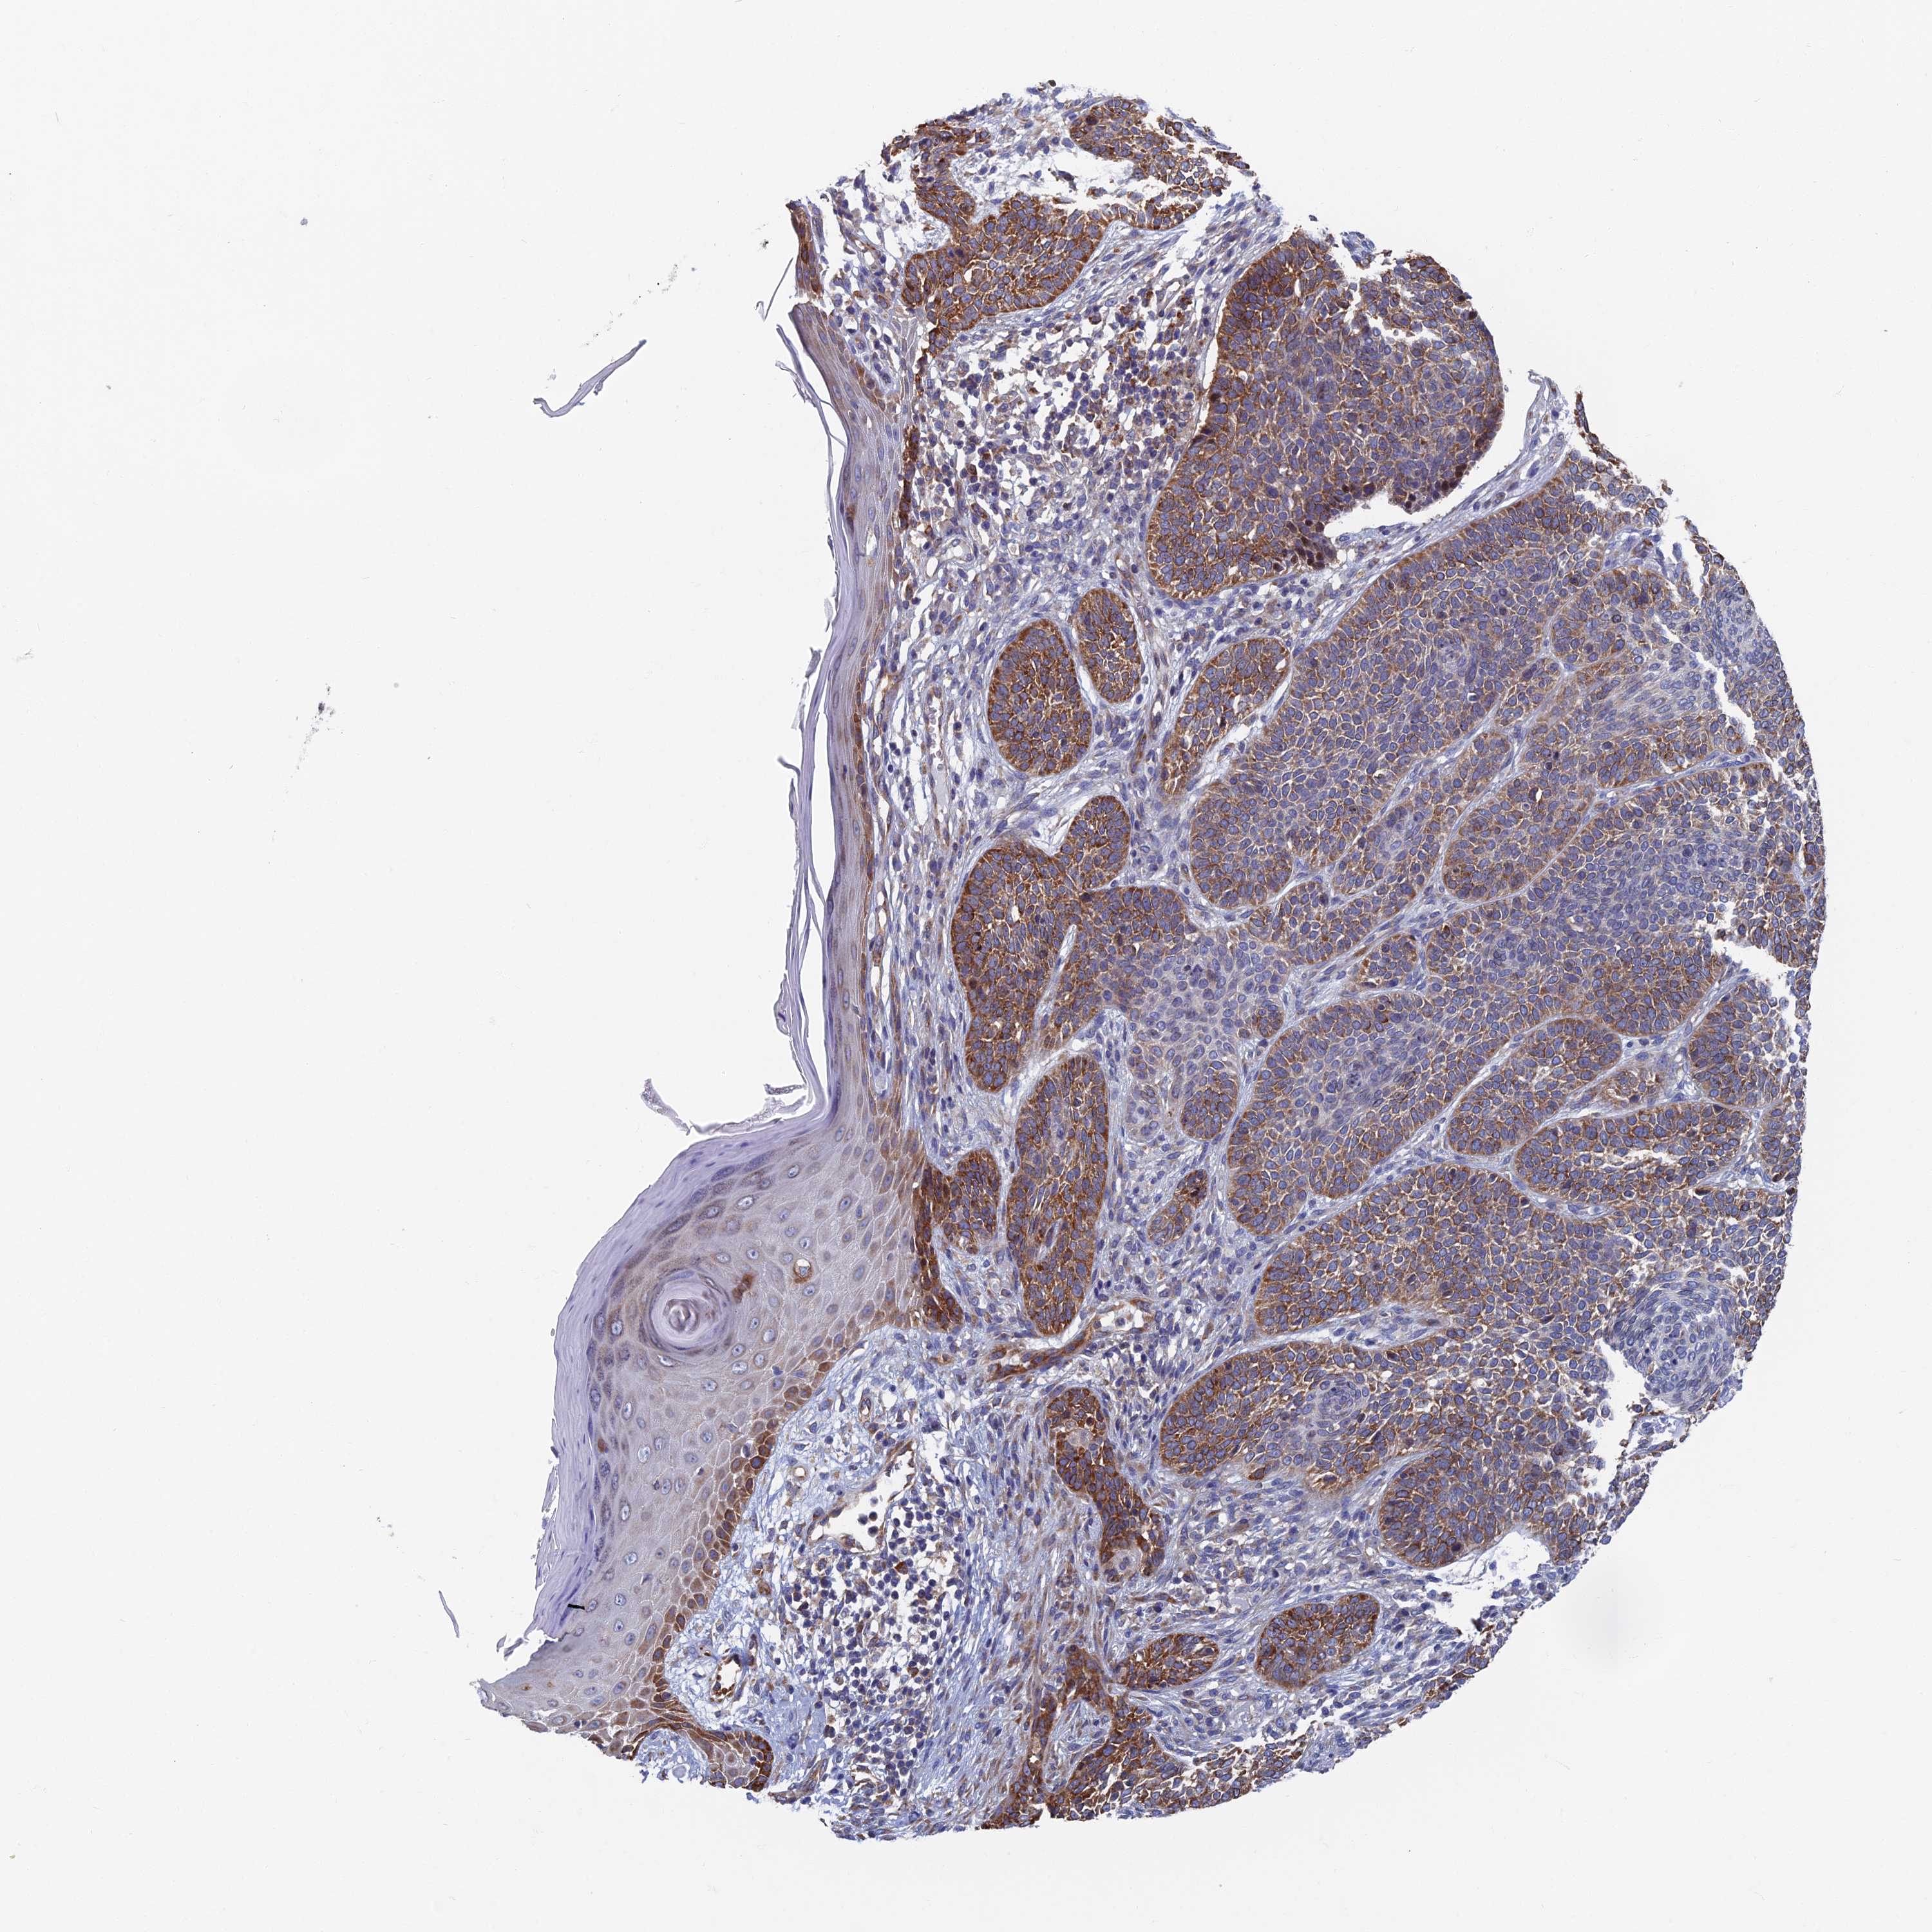

SKIN CANCER - Protein expressioni

A mouse-over function shows sample information and annotation data. Click on an image to view it in a full screen mode. Samples can be filtered based on level of antibody staining by selecting one or several of the following categories: high, medium, low and not detected. The assay and annotation is described here.

Antibody stainingi

Antibody staining in the annotated cell types in the current human tissue is reported as not detected, low, medium, or high, based on conventional immunohistochemistry profiling in selected tissues. This score is based on the combination of the staining intensity and fraction of stained cells.

Each image is clickable and will lead to virtual microscopy that enables deeper exploration of all samples and also displays staining intensity scores, fraction scores and subcellular localization as well as patient and tissue information for each sample.

Antibody HPA040304

Basal cell carcinoma